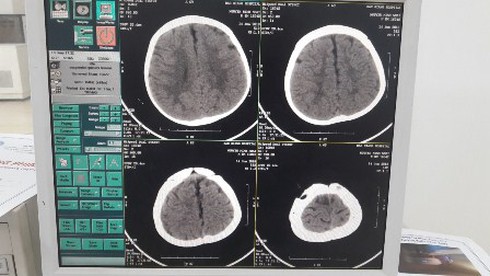

Bệnh nhi là cháu Nguyễn Minh Nhật 8 tháng tuổi ở Yên Dũng, Bắc Giang. Theo lời kể của gia đình, do không may cháu bị ngã từ trên giường, đập đầu xuống nền cứng. Sau ngã trẻ quấy khóc, sưng nề tụ máu dưới da đầu vùng thái dương đỉnh phải. Gia đình đã đưa cháu đến BVĐK tỉnh Bắc Giang. Kết quả Chụp X- quang và cắt lớp vi tính sọ não cho hình ảnh: Vỡ lún xương sọ vùng thái dương đỉnh phải. Bệnh nhân được chỉ định phẫu thuật nâng xương vỡ lún qua da.

Hình ảnh sọ não trước can thiệp |